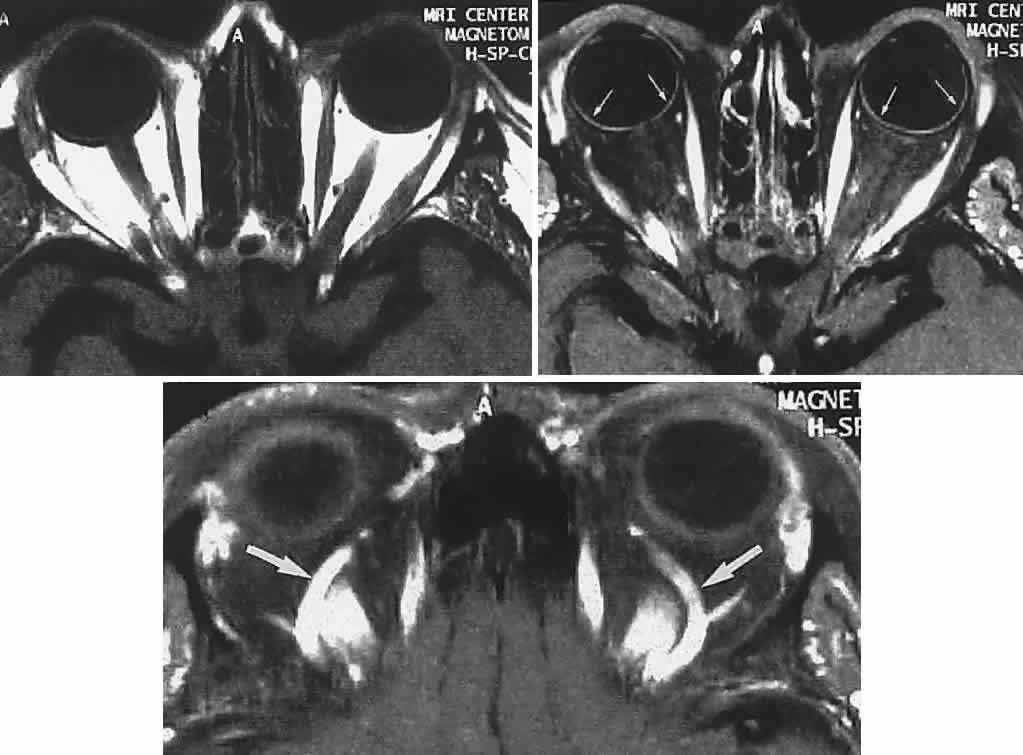

Now almost universally available, MRI is the preferable technique for imaging the soft tissue contents of the orbit, high-resolution 3-mm and thinner sections being available, as well as gadolinium contrast enhancement (Figs. 19, 20, and 21).

Fig. 19. MRI of orbits, axial sections. Top. T1-weighted: orbital fat is white (hyperintense), muscles are dark. Middle. Fat saturation with gadolinium through midorbit: orbital fat signal suppressed (dark), accentuates hyperintense muscles; note also choroid (small arrows). Bottom. Fat-saturation technique through superior aspect of orbit; note superior ophthalmic veins (arrows).

Fig. 20. MRI of orbits, coronal sections. Fat suppression. Top. Midorbit. Middle. Orbital apex. Bottom. T2-weighted. Arrows indicate optic nerve; note ring of CSF (bottom).